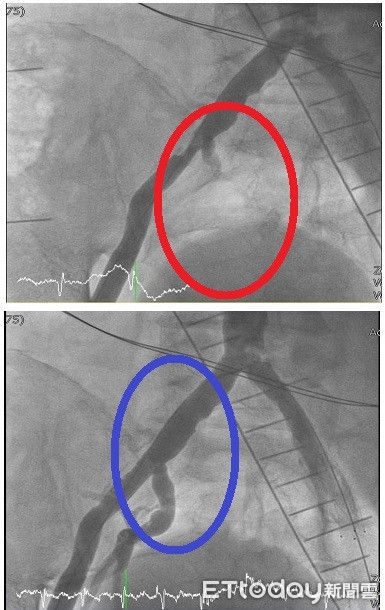

▲謝男經進行週邊血管成形術及放置支架治療後,謝先生動脈阻塞(紅圈處)順利恢復(藍圈處),疼痛感大幅感善。(圖/大千綜合醫院提供)